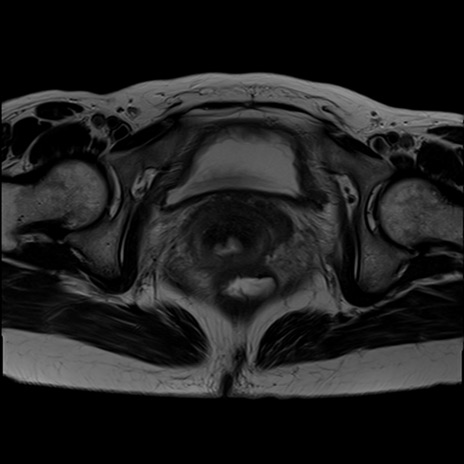

症例39 T2WI(横断像)

MRI(4日後)